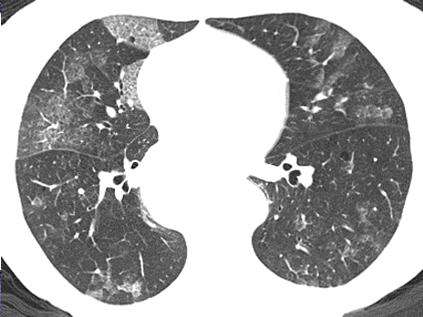

間質性肺病(Interstitial lung Disease,簡稱ILD) 是以彌漫性肺實質、肺泡炎和間質纖維化為病理基本改變,以活動性呼吸困難、X 線胸片示彌漫陰影、限制性通氣障礙、彌散功能(DLCO)降低和低氧血癥為臨床表現的不同類疾病群構成的臨床病理實體的總稱。ILD 通常不是惡性的,也不是由已知的感染性致病源所引起的。繼發感染時可有黏液濃痰,伴明顯消瘦、乏力、厭食、四肢關節痛等全身癥狀,急性期可伴有發熱。